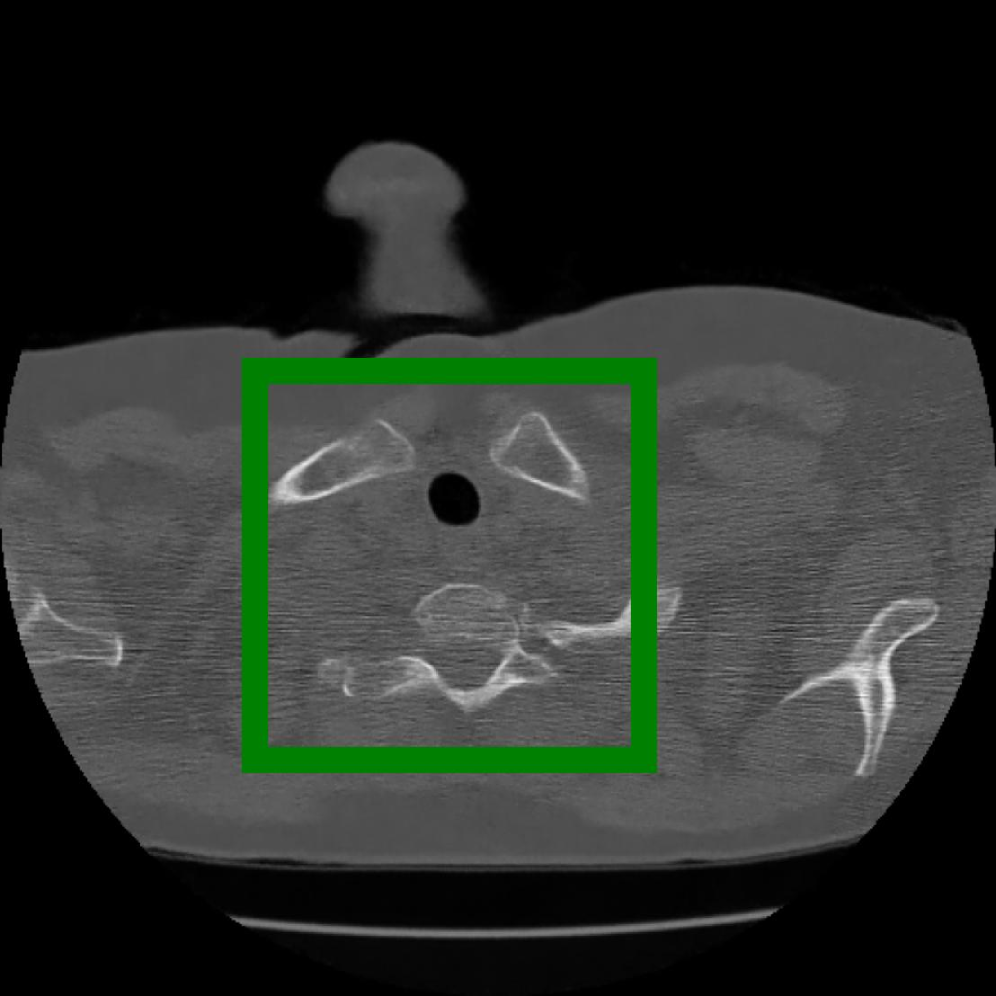

Figure 10: The visual comparison of different compression methods on a CT Heart Segmentation image.

Figure 11: Zoomed-in view of the highlighted region in Figure 10.

Figure 12: The visual comparison of different compression methods on another CT Heart Segmentation image.

IV-B3 Visual Comparison

Figures 7 and 8 present representative examples from the CIL dataset and their zoomed-in regions, respectively. For the CT Heart Segmentation dataset, Figures 10 and 12 illustrate typical reconstruction results, while Figures 11 and 13 further enlarge local regions to compare structural details. Across both datasets, COLI preserves fine structures and global continuity well even at relatively low bpp. Specifically, on the CIL dataset, COLI attains the lowest bitrate among INR-based methods while still maintaining clear texture details. On the CT Heart dataset, COLI also operates at a low bpp within the INR family and delivers superior visual quality with improved detail fidelity and smoother structural presentation. The zoomed-in regions show fewer blocking artifacts and smoother transitions, making COLI especially suitable for large images and medical images. These visual results validate that INR-based compression can achieve efficient storage with reliable perceptual consistency, offering practical advantages for real-world large-scale image processing.